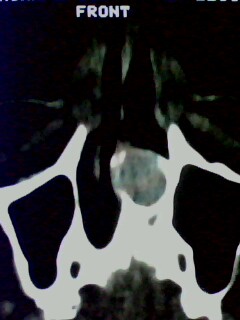

以下是引用随光逐影在2009-5-20 19:22:00的发言:[br]1)考虑左上颌骨近中线区含牙囊肿。2)鼻中隔右突偏曲。3)双侧下鼻甲肥大。